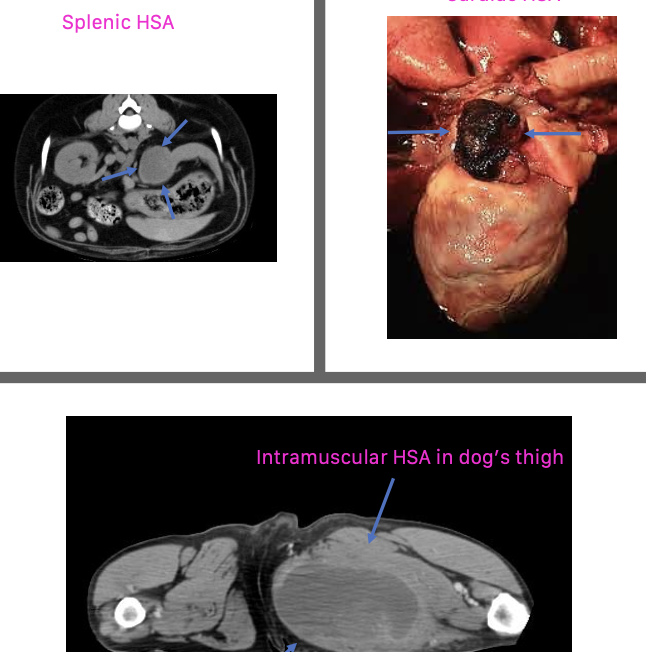

what are common locations of primary hemangiosarcoma?

can occur anywhere:

1. visceral

2. cardiac

3. dermal/SQ/intramuscular

what are the common primary visceral sites of hemangiosarcoma?

-spleen is the most common location

-liver

-other: kidney, retroperitoneal space, nasal cavity, oral cavity, bone

what are the common primary cardiac sites of hemangiosarcoma?

second most common primary site:

-right atrium

-right auricle